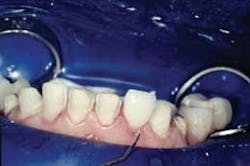

The excess cement is removed with a Bard Parker 12B scalpel blade. Minimal polishing is done with Sof-Lexâ„¢ Extra Thin Superfine Discs (3M ESPE) and Flexibuffsâ„¢ with Porcelize polishing paste (Cosmedent). The remaining veneers are seated in pairs following the same protocol (Fig. 9).